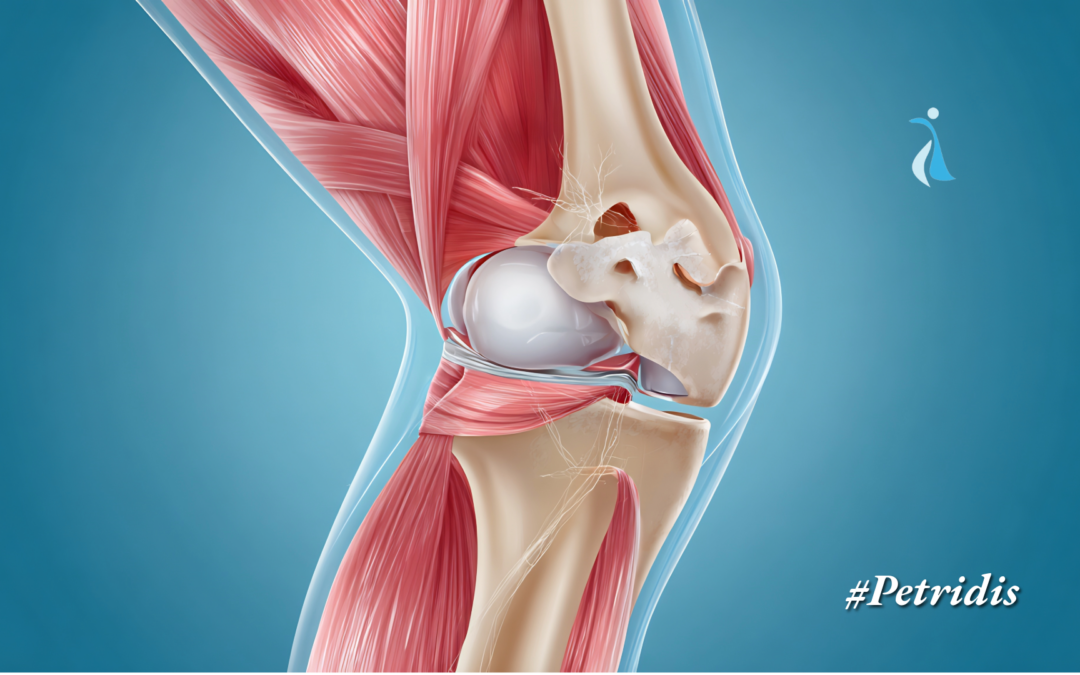

Η ρήξη πρόσθιου χιαστού συνδέσμου (ΠΧΣ) είναι μία από τις πιο συχνές κακώσεις του γόνατος στους ενήλικες, όχι μόνο σε αθλητές αλλά και σε άτομα που τραυματίζονται σε καθημερινές δραστηριότητες.

Πότε είναι απαραίτητο το χειρουργείο – Πρόσθιος Χιαστός Σύνδεσμος

Συνοδές βλάβες – Πρόσθιος Χιαστός Σύνδεσμος

Όταν η ρήξη του ΠΧΣ συνυπάρχει με ρήξη μηνίσκου ή βλάβες χόνδρου, η χειρουργική αποκατάσταση συστήνεται άμεσα ώστε να προστατευθεί το γόνατο.

Συμπέρασμα – Πρόσθιος Χιαστός Σύνδεσμος

Η χειρουργική αποκατάσταση του πρόσθιου χιαστού δεν είναι πάντα απαραίτητη, αλλά για πολλούς ενήλικες με ενεργό τρόπο ζωής αποτελεί τη μόνη λύση για ένα σταθερό και λειτουργικό γόνατο.